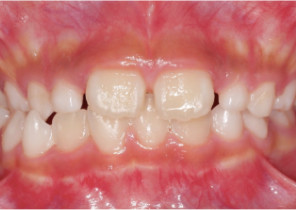

Case Report 2

7 years 11 months old, 24 stages of Invisalign® Palatal Expanders

Courtesy of Dr. David R. Boschken

Post Invisalign Palatal Expander Treatment